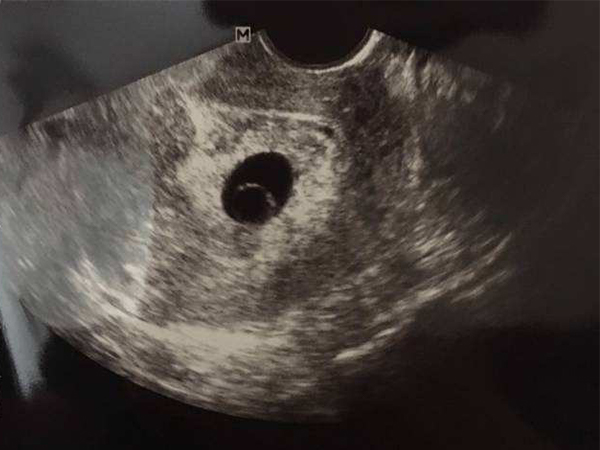

卵黄囊和孕囊的区别B超首次为你揭露其形状

卵黄囊是母体和胚胎交换的最初始途径,它位于孕囊里面,两者是有本质上的区别,而后随着孕周增加,卵黄囊的大小形状也不一样,在临床上通过B超检查,如果确定宫内有孕囊,..

卵黄囊和孕囊区别大,透过B超首次为你揭露其形状